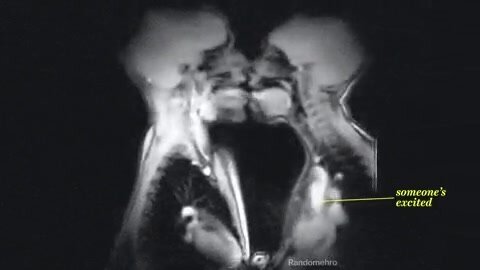

Поцелуй ,как он выглядит?